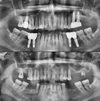

أمراض الأسنان واللثة